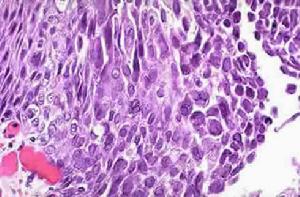

病理改變:肺組織有炎性浸潤,肺實質壞死,出血,細胞腫脹變圓,瀰漫性間質性肺炎且大部分伴有皰疹病毒感染的細胞改變特徵如核內嗜酸性包涵體,可有壞死性單純皰疹病毒性氣管炎或單純皰疹病毒性食道炎。單純皰疹病毒性支氣管炎,表現為黏膜紅斑、水腫、滲出和潰瘍,表面可覆蓋有纖維膿性膜樣分泌物。

HSV肺炎的臨床表現和放射學表現為非特異性。單純皰疹病毒性肺炎的診斷,除肺炎臨床表現外,須依靠HSV肺部感染的組織學依據和肺部病毒的分離。直接從下呼吸道分離出病毒最好從肺組織,具有明確的診斷意義。氣管鏡檢查結合細胞學檢查和病毒培養有診斷意義,雖然並非必須,但可提供組織標本。纖維支氣管鏡檢查顯示氣管支氣管黏膜潰瘍和(或)覆蓋有假膜,該檢查可引導抽吸支氣管沖洗或活檢。細胞學和組織學檢查可提供HSV感染的特異性證據:多核巨細胞和核內嗜酸性包涵體。另外活檢標本檢查示炎性浸潤,實質壞死和出血。